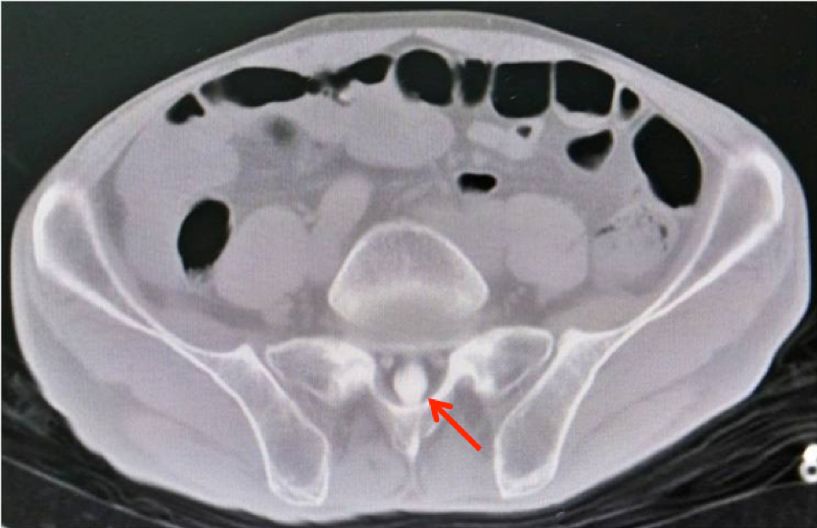

考虑重水在蛛网膜下腔和脑室内多发散在分布,为促使重水从颅内迁移入腰椎椎管,并最终经腰穿予抽出,反复多次更换体位,椎管CT检查,显示脊柱胸髓段及骶管内高密度影,证实多数重水已迁移入腰骶管内(图2)。

图2. 椎管CT平扫示:脊柱胸髓段及骶管内高密度影,提示重水已大部分迁入腰骶管。